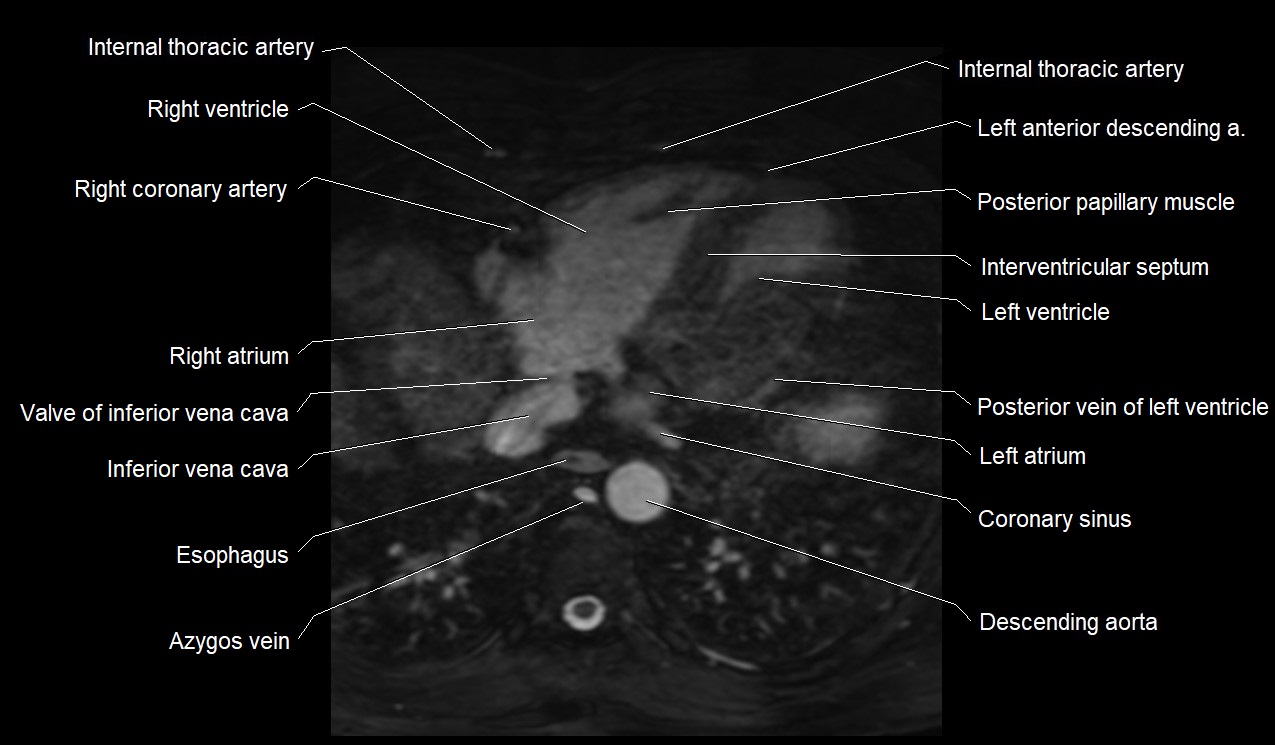

MRI image